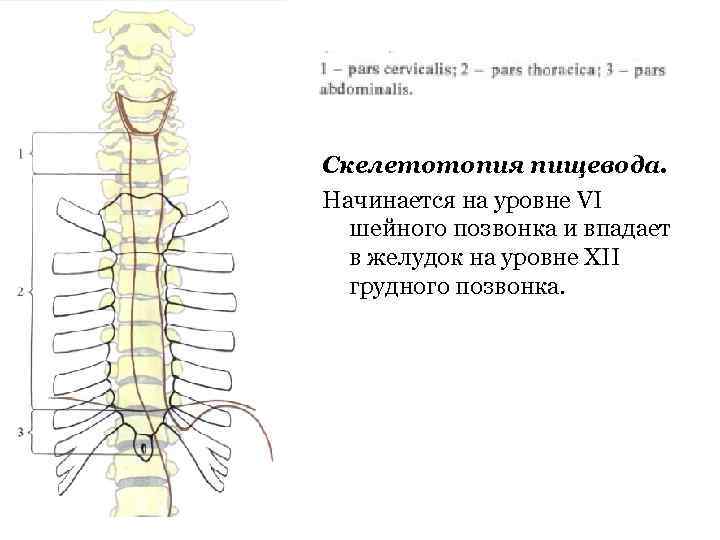

Пищевод (oesophagus) – полый трубчатый орган. Длина у взрослого человека – 25 -27 см. Pars cervicalis. 5 -7 см. Pars thoracica. 16 -18 см. Pars abdominalis. 1, 5 -4 см.

Пищевод (oesophagus) – полый трубчатый орган. Длина у взрослого человека – 25 -27 см. Pars cervicalis. 5 -7 см. Pars thoracica. 16 -18 см. Pars abdominalis. 1, 5 -4 см.

Скелетотопия пищевода. Начинается на уровне VI шейного позвонка и впадает в желудок на уровне XII грудного позвонка.

Скелетотопия пищевода. Начинается на уровне VI шейного позвонка и впадает в желудок на уровне XII грудного позвонка.